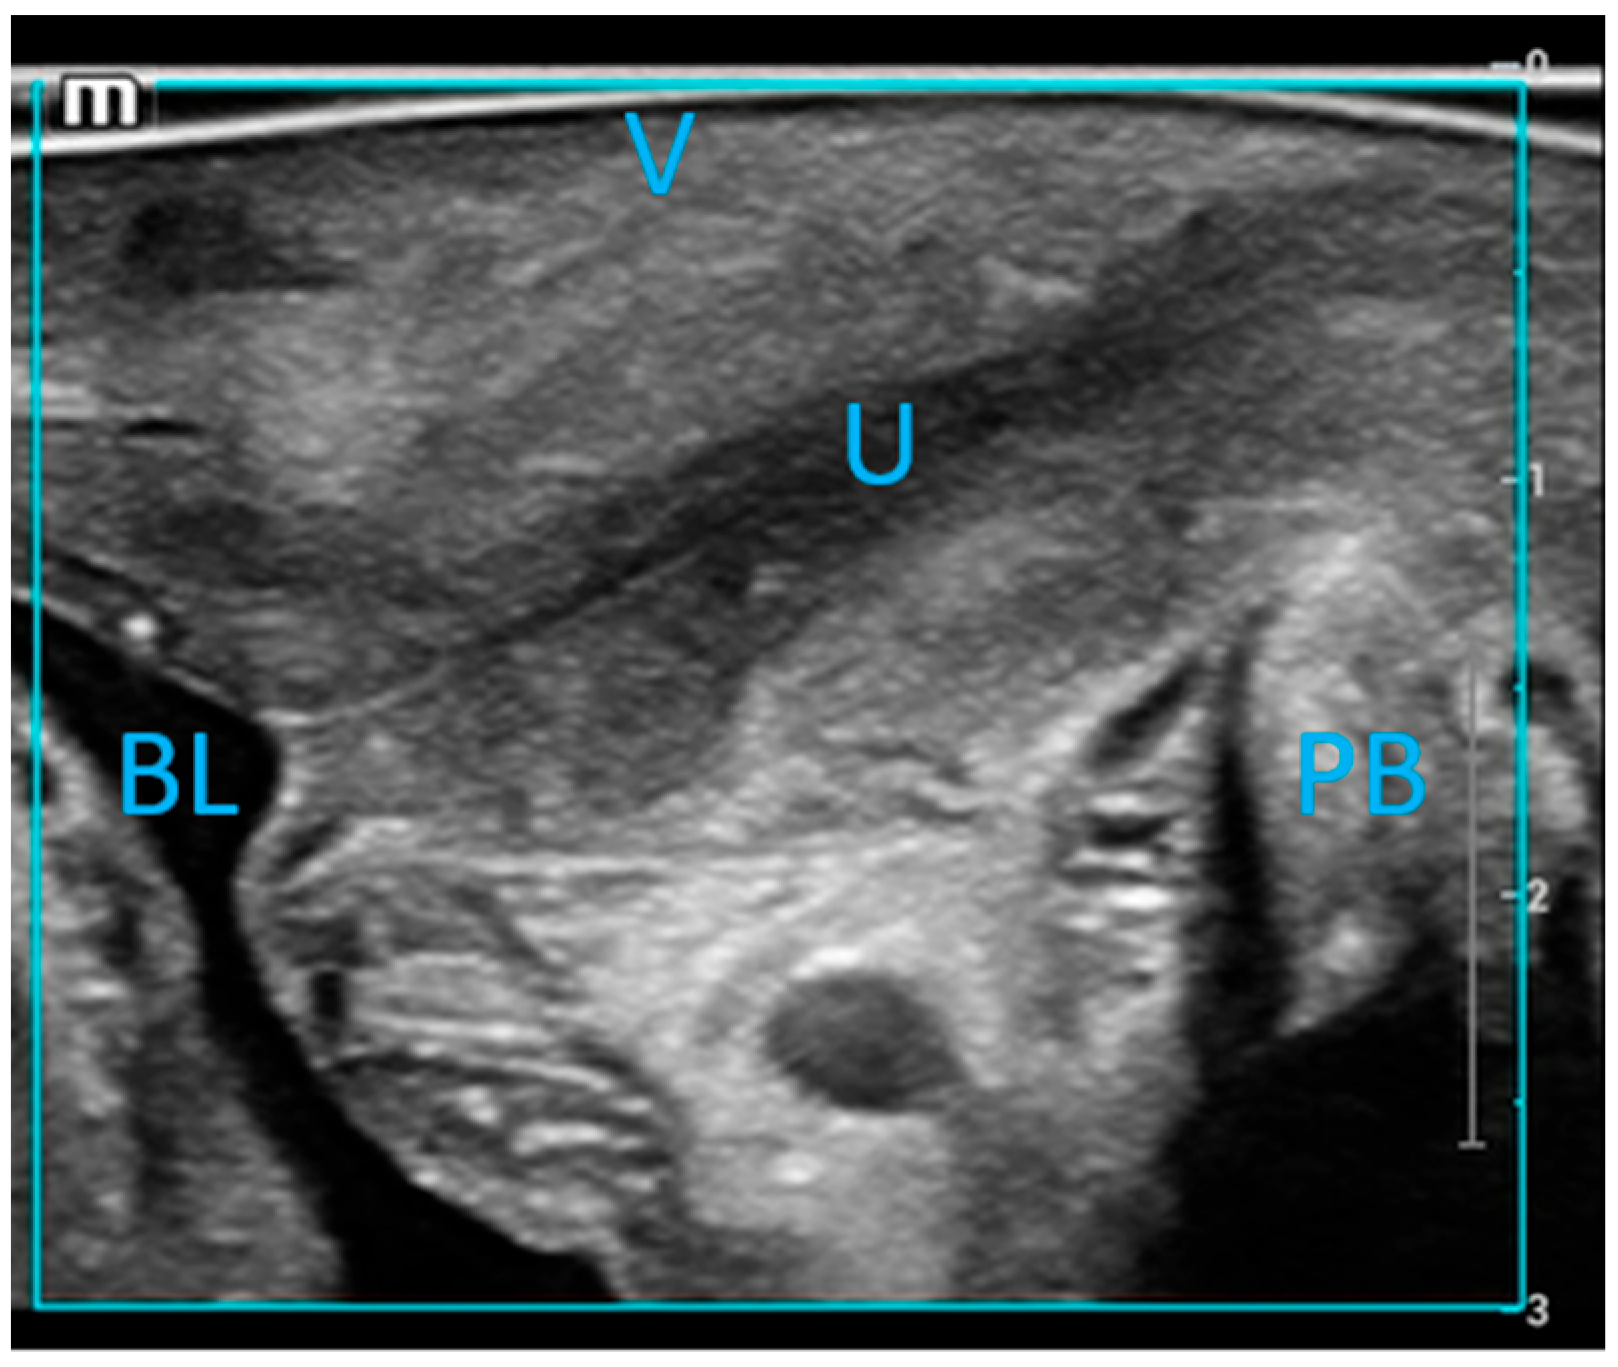

2.2. Ultrasound Examination